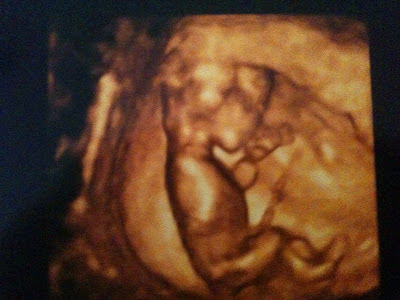

He/she is measuring right on track at 12 weeks and 3 days, and his/her heartrate was 171 bpm. The doctor said all of baby's measurements look great! We are just so elated, I can't even put it in words.

The tech was kind enough to print us 5 pictures, here are my two favorites:

We were lucky enough to be in the one ultrasound room (out of a dozen) that had the 3D scanning capability. How awesome is the 3D picture?